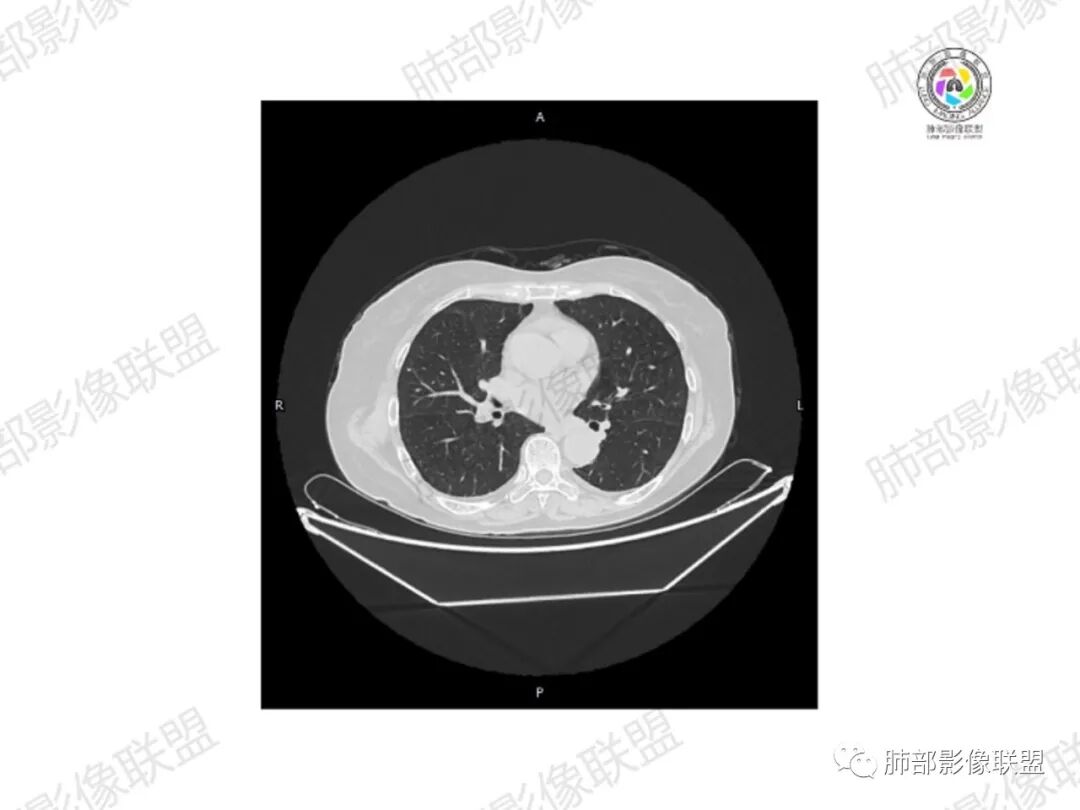

5.双肺多发类圆形结节影,边界清楚,随机分布,其间多见钙化密度影。

6.双肺门及纵隔未见肿大淋巴结。

3.双肺病灶符合转移瘤,伴有中央部分钙化者也以骨肉瘤转移较为多见。